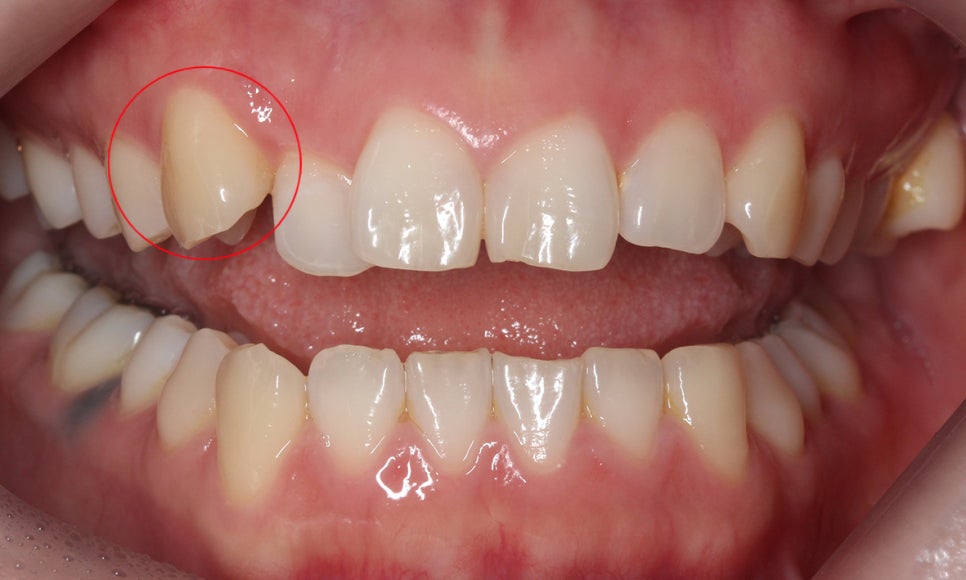

아래의 Case는 상악 송곳니에 덧니증상이 나타난 경우로

송곳니는 치아의 맹출 순서에 영향을 받아 덧니로 자랄

가능성이 높다고 볼 수 있습니다.

정면에서 바라본 치아의 모습을 보시면

상악 우측 송곳니가 주변 치아들보다 높은

위치에 뻐드러져 자라난 것을 확인할 수 있는데요,

덧니를 확인하는 가장 간단한 방법인

치아가 자라난 높이를 확인하는 방법으로

송곳니 양쪽의 치아들보다 높은 위치에서

맹출된 모습을 볼 수 있습니다.

이러한 덧니의 높이를 확인하는 방법은

자칫 덧니교정으로 착각할 수 있는

치아틀어짐과 확실하게 구별되는 증상으로

환자분들도 육안으로 손쉽게 확인하실 수 있습니다.